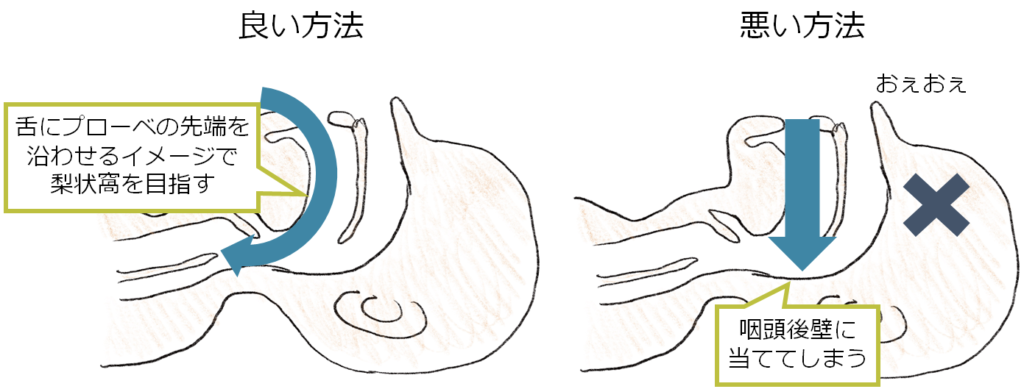

3D心エコー:どうやって使えば手術に役立てられるか? 解剖学的。循環器内科医のための経食道心エコー〜基本的な手技から術中・術。figure4.image1.png。ご覧いただきありがとうございます。「経食道心エコー II」の出品です。- タイトル: 経食道心エコー II- 監修者: 野村実- 編集者: 国沢卓之- 定価: 12,500円+税【状態について】以下、コンディションの詳細です。写真も併せてご確認ください。■カバーの状態:【 良 】目立つ傷や汚れなし■表紙・裏表紙の状態:【 良 】比較的綺麗■ページの状態:【 良 】書き込み・マーカー・目立つ汚れなし【ご購入について】・即購入OKです。・中古品であることをご理解の上、ご購入をお願いいたします。・ご不明な点は、お気軽にコメントください。【発送について】・梱包:OPP袋で防水対策をし、封筒に入れて発送します。・発送方法:佐川急便/日本郵便(ネコポス)を予定しています。匿名配送です。・発送までの日数:通常、ご購入(お支払い確認後)から1~2日以内に発送いたします。丁寧な検品と梱包を心がけております。よろしくお願いいたします。#経食道心エコー#TEE#循環器#心臓血管外科#医学書。循環器内科医のための経食道心エコー〜基本的な手技から術中・術。矯正歯科治療におけるスマイルデザインと審美処置。裁断済 在宅医療 藤田総診リアル実践ガイド たんぽぽ先生の在宅報酬算定マニュアル。インナービューティーダイエット プレミアム レシピ。口腔病理アトラス 第三版。救急救命スタッフのためのITLS。視能訓練士 国家試験問題集 第43〜48回 2019年発行。心電図検定参考書。【裁断済み】四肢切断術のすべて。麻酔科プラクティス 周術期呼吸管理。臨床検査技師 ポケットマスター。絵でみる和漢診療学。CBT・医師国家試験のための レビューブック 産婦人科 2022-2023